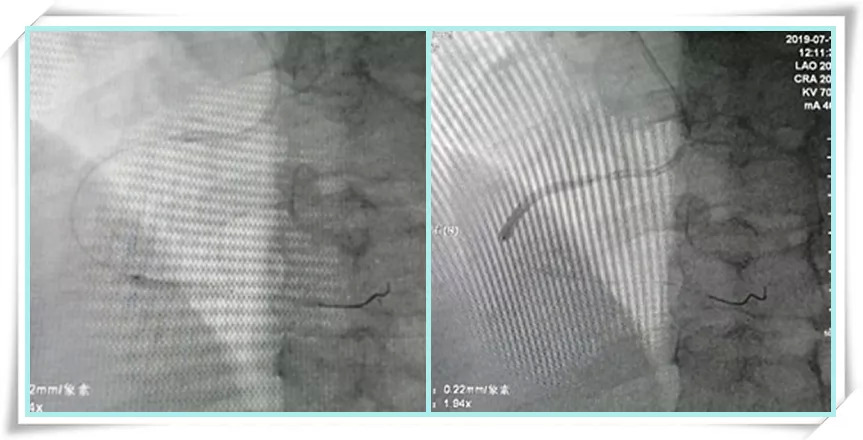

定位支架着陆点,确定支架尺寸。

释放支架